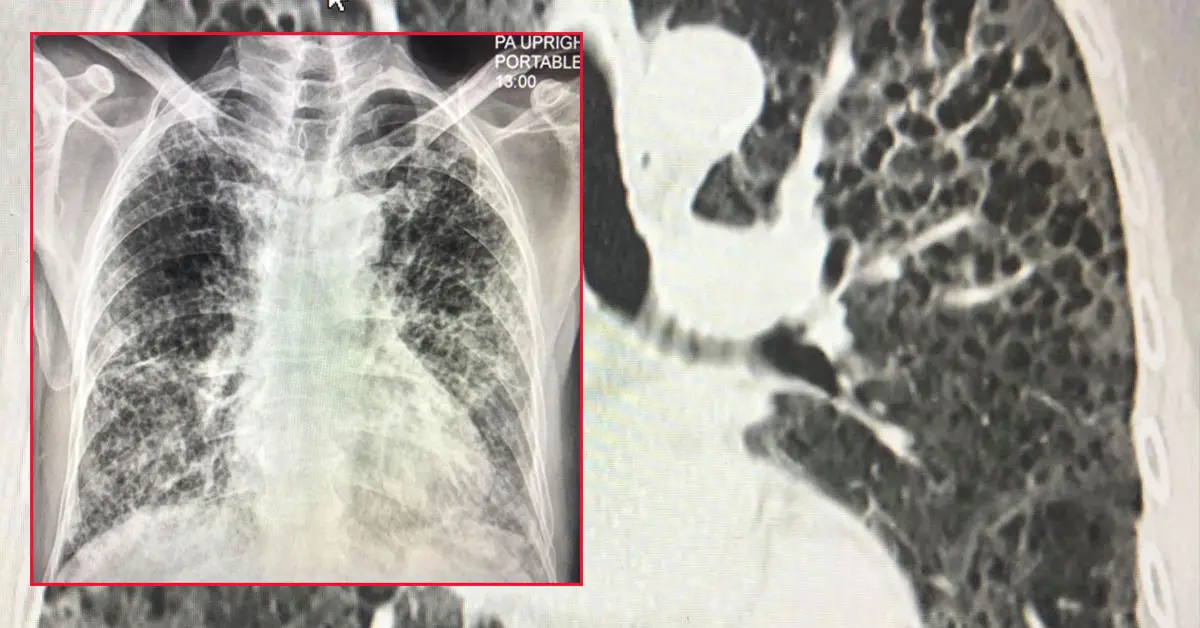

ผู้ป่วยชายไทยอายุ 80 ปี ปกติแข็งแรงดี ไม่มีประวัติป่วยเป็นโรคปอด ไม่สูบบุหรี่ เมื่อวันที่ 16 เมษายน 2564 ป่วยเป็นโรคโควิด-19 โดยลูกเป็นคนนำเชื้อมาให้ผู้ป่วยและคนในครอบครัวรวมทั้งหมด 7 คน เข้านอนรักษาในโรงพยาบาลด้วยปอดอักเสบรุนแรง เอกซเรย์ปอดมีฝ้าขาวทั้ง 2 ข้าง (ดูรูป) ทำคอมพิวเตอร์สแกนปอดพบเนื้อเยื่อปอดอักเสบรุนแรง มีทั้งฝ้าขาว รอยโรคเหมือนร่างแห และลักษณะผิดปกติคล้ายรังผึ้ง กระจายทั่วปอด (ดูรูป) ผู้ป่วยได้รับการรักษาเต็มที่ โชคดีที่ไม่ต้องใส่เครื่องช่วยหายใจ ต้องใช้ออกซิเจนมากถึง 10 ลิตร/นาทีตลอดเวลา นอนในรพ.ถึงวันที่ 22 พฤษภาคม 2564

8 สัปดาห์หลังจากเริ่มป่วย มีไอเล็กน้อย ไม่มีไข้ เดินนิดเดียวก็เหนื่อย ยังต้องใช้ออกซิเจน 4 ลิตร/นาทีตลอดเวลา ระดับออกซิเจนในเลือดถึงจะขึ้นมาอยู่ที่ 95% แต่ถ้าไม่ใช้ออกซิเจน ระดับออกซิเจนในเลือดจะลดลงต่ำกว่า 80% เอกซเรย์ปอดยังผิดปกติ ลักษณะคล้ายพังผืด แต่ดีขึ้นช้าๆ (ดูรูป)ไวรัสโควิด-19 มีผลกระทบระยะยาวต่อปอด (Post-Acute Sequelae of SARS-CoV-2 infection)